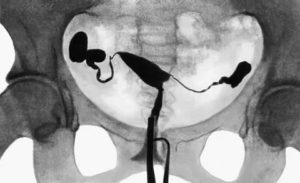

ГСГ предполагает выполнение серии рентгенологических снимков. Их делают после того, как в трубы будет введено контрастное вещество. В диагностике принимают участие два врача – рентгенолог и гинеколог. Перед проведением обследования женщине потребуется сдать анализы. Важно исключить беременность, воспалительные процессы, маточное кровотечение, опухоль труб и наличие аллергии на йод.

Обратите внимание, на картинке одна маточная труба непроходима. Контраст просто не может пройти сквозь спайки.

Делается это с помощью тончайшего катетера. Заполнив орган, раствор попадает в трубы. В это время доктор делает снимок. Если контрастное вещество равномерно распределилось по трубам, то спаек в них нет.

Если была заполнена только одна труба, то вторая считается непроходимой. Врач имеет возможность увидеть, в каком именно месте остановился раствор.